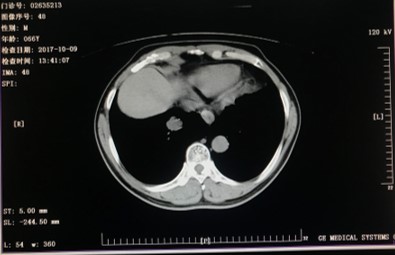

2017年10月-2018年1月:XELOX方案化疗4周期。(奥沙利铂180mg 卡培他滨1.5g bid)